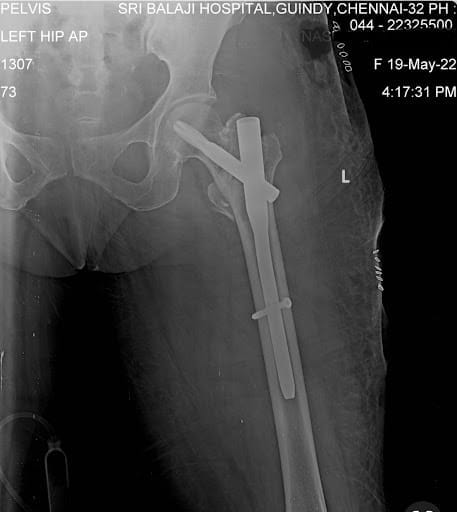

These fractures usually occur close to the hip joint (the ball and socket joint). These fractures most commonly affect the upper part of the thigh bone (inter-trochanteric fractures) nearer to the ball of the ball & socket joint (neck of femur fracture). A rarer form of hip fracture involves a crack or fracture to the socket (acetabulum) of the ball and socket joint.

Fractures to Upper Thigh Bone

These fractures involve the breaking of the upper part of the thigh bone (femur).

Cause of injuries:

Slip & fall while walking. The severity of the fractures depends on the intensity of the fall as well as the strength of the bone.

Preferred treatment option:

Undisplaced stable fractures can be treated conservatively with bed rest for 4-6 weeks.

Unstable fractures and multi-fragmentary fractures are treated using “keyhole” surgery known as proximal femur nailing under ultrasound-guided regional Anesthesia (wide awake surgery)

Recovery time:

As mentioned above, in stable fractures treated conservatively, the patients are usually suggested 6 weeks of bed rest before starting out-of-bed mobilisation activities.

Here at Sri Balaji Hospital, individuals who have sustained unstable fractures and subsequently undergone key-hole surgery known as Proximal Femur Nailing (PFN) are often made to walk anytime within 24 hours, and once mobilised, they can walk as much as they like.